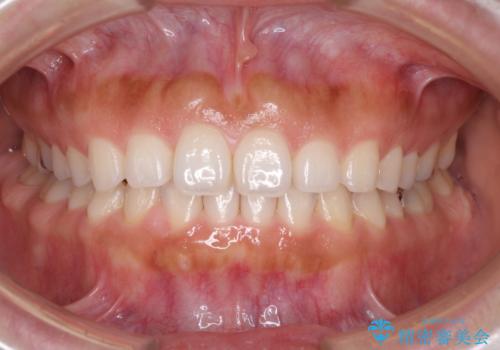

隙間の空いた前歯を閉じたい インビザライン矯正

- 前歯の隙間を気にして来院された患者様です。

隙間、捻転ともに軽微でありましたが、下顎前歯の突き上げにより隙間ができていたため、インビザラインを用いて咬み合わせを改善しながら前歯の歯列を整えていくこととしました。

当初は1年程度で終えられると思いましたが、治療途中から装着時間が短くなったり、来院間隔が長期になったりとし、結果として4年半以上の治療期間となりました。

治療途中に上顎前歯は失活してしまいましたが、変色が顕著ではないため、経過を見ていくこととなりました。